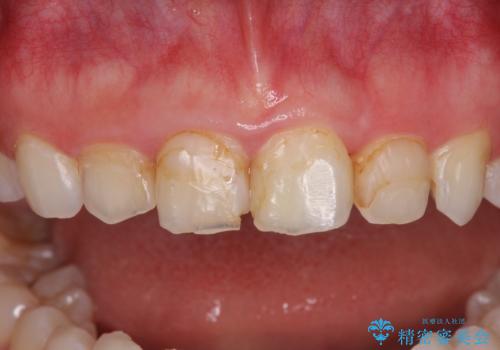

- 前歯の歯並びと虫歯を気にして来院された患者様です。

上下前歯の歯列不正はインビザラインにより歯列を整え、その後に、前歯5本をオールセラミッククラウンにて補綴治療することとしました。

矯正治療前に前歯のむし歯治療を行ったものの、樹脂で充填するには虫歯が広範囲であったため、審美的に問題がありました。

矯正治療にて歯並びを整えた後に、虫歯の大きかった5本の歯をセラミッククラウンにて補綴し、明るい口元になりました。